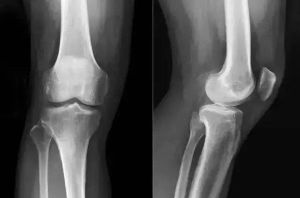

3、嚴重者膝關節腫脹,關節積液,晨僵及久坐後膠著,關節伸屈功能障礙,上下台階、久立時,膝關節症狀加重。少數病人可見關節積液,局部有明顯腫脹、壓縮現象,膝其中關節前內側條索樣腫塊伴伸膝障礙,膝關節周圍骨贅形成,關節周圍伴有骨質疏鬆與骨質硬化。

4、關節間隙變窄,關節面毛糙不平,其內側脛骨關節面受累明顯,關節間隙變窄。其中多數會發生內側間隙狹窄,髕骨骨刺形成。